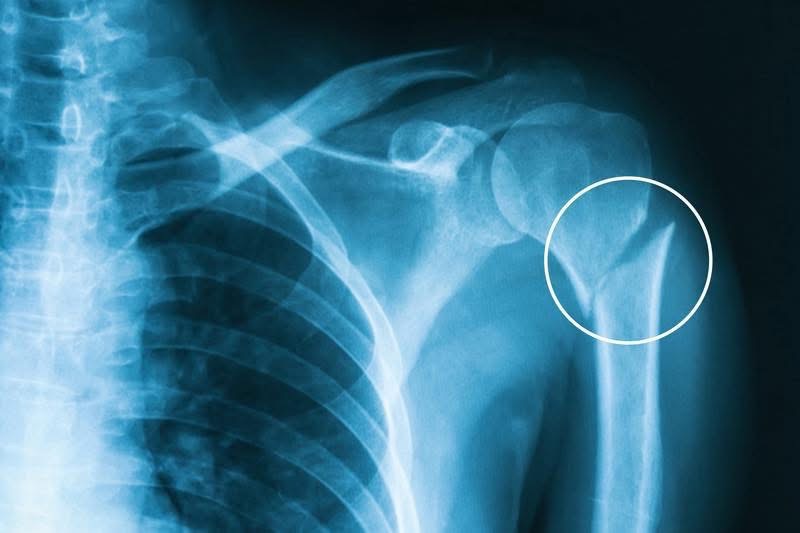

My name is Chelsea, and I’m fundraising on behalf of my friend JC Kennedy. On November 17, JC sustained multiple injuries from a bad skating accident when he had to quickly veer to avoid running into his client who had also fallen while skating downhill. He has an anterior shoulder dislocation, his humerus is broken in two places, he had to get eleven stitches above his left eye, and he is likely facing surgery in the near future. He is receiving care through Saint Joseph Providence in Burbank and is following all of their guidance. Although the timeline and outcome are unclear, he is maintaining his positive attitude and hopes to be able to return to skating after his recovery.